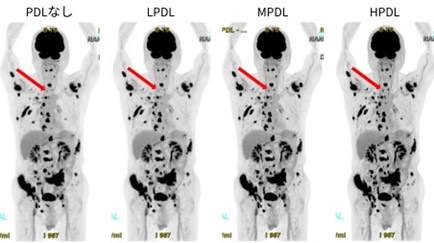

このPrecision DLは処理強度をLow, Medium, Highの3 段階から選択することができ、複数の強度で再構成を行うよう設定することも可能です。それぞれの画像を比較すると、Highではよりシャープな画像となり、Lowではノイズの少ない滑らかな画像となります(図 5)。実際の病変集積で比較すると、いずれのPDL強度でも微少な集積のコントラスト向上が確認されましたが、特にHighの画像では5 mmの骨転移の病変がより明瞭に描出されています。

図 5. Precision DL比較画像 (→肺癌 骨転移 5 mm 病変)